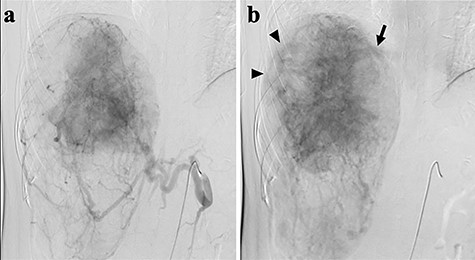

A 45-year-old woman was referred to our hospital with a huge liver tumor, which had been diagnosed as HAML 5 years previously when it was 12 cm in diameter (Fig. 1). Periodic follow-up with ultrasound and magnetic resonance imaging after the initial diagnosis had shown a progressive increase in the size of the tumor, and by the time of referral it measured 20 × 14 cm and had become symptomatic. On admission, enhanced computed tomography revealed a very large, well-defined, mixed-density mass occupying the entire right lobe of the liver (Fig. 2). Angiography showed dilated and tortuous vessel inside the tumor, and a drainage vein from the tumor to the right hepatic vein was visualized in the early phase (Fig. 3).

Abdominal angiography; (a) hepatic angiography shows a hypervascular tumor with a fine network of vessels in the arterial phase; (b) dilated and tortuous vessels (arrow heads) were noted inside the tumor, then a drainage vein to the right hepatic vein (arrow) was visualized in the early phase.

Radiological diagnosis of HAML is occasionally difficult since the proportion of adipose tissue in the tumor varies greatly, ranging from 5 to 90% [1]. The typical radiological criteria for HAMLs are: (i) high vascularization of in a solid tumor and (ii) presence of macroscopic fatty components [2]. An early drainage vein around the tumor may also be very helpful for diagnosis [3–4]. In a study of 47 patients with HAML, Nonomura et al. [5] demonstrated that abnormally large, dilated blood vessels were present around the tumors at the tumor-background liver interface in 40% of the HAMLs they examined. This feature was not found in tumors < 25 mm in diameter, but was present in 60% of HAMLs with a diameter of ≥25 mm. In the present case, imaging modalities showed these typical findings, enabling the diagnosis of HAML.